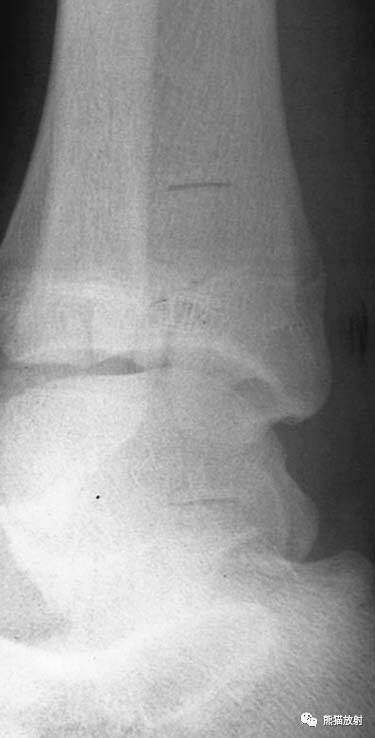

(上图)骨骺轻微向背侧、内侧移位,1-2周后随访骺板处可见成骨反应。

Salter-Harris I型:干骺端及骨骺分离

平片通常为正常,可表现为骺板增宽或骨骺轻度移位。

(上图)胫骨远端骺板变窄,同时可见并发的跟骨骨折。

Salter-Harris V型:由轴向压力导致的挤压伤,表现为骺板的明显扭曲或变窄。